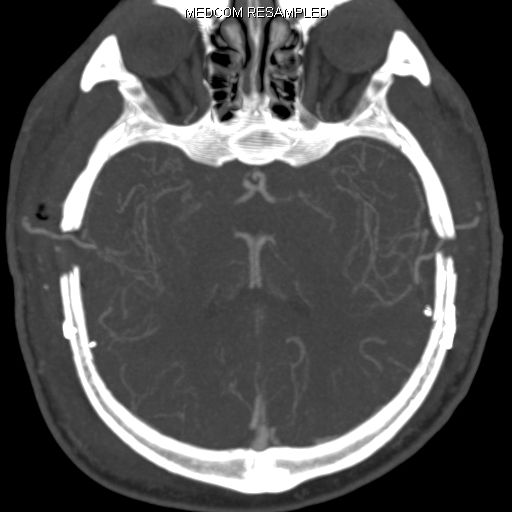

Die wichtigste Untersuchung zur absoluten Darstellung des Blutflusses im Gehirn im Ruhezustand (baseline) und nach medikamentös stimulierter Gefäßweitstellung ("Diamox/Acetazolamid-Challenge") ist das sogenannte Wasser (H2 15O) PET/CT. Bei dieser Untersuchung wird eine definierte Menge kurzzeitig radioaktives Wasser in das Blutsystem appliziert und somit kann die absolute Blutmenge im Gehirn für jedes Gefäßterritorium bestimmt werden. Dies erfolgt dann sowohl im Ruhezustand und nach Medikamentengabe. Somit kann man die cerebrale Perfusionsreserve absolut darstellen und an Hand dessen Gefäßterritorien mit benötigter Revaskularisation (Anlage eines Bypasses) identifizieren. Auf Grund des benötigten speziellen Nuklearmedizinischen Setups kann diese Untersuchung nur an wenigen Orten in Deutschland durchgeführt werden. Hierfür kooperieren wir mit der Nuklearmedizin der Universität in Freiburg.

PET-CT nach Diamox Gabe

PET-CT nach Diamox Gabe zeigt eine einseitig deutlich reduzierte Perfusionsreserve (grüne Farben) im Vergleich zur Gegenseite mit ausreichendem Anstieg der Durchblutung (warme Farben).